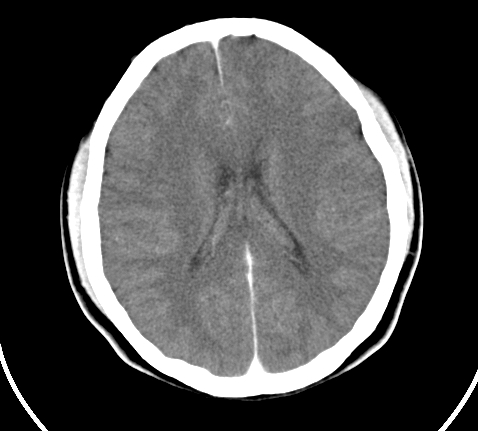

标题: CT23915:女 20岁 全身长疙瘩三年 今日多体位查 看看吧 [打印本页]

标题: CT23915:女 20岁 全身长疙瘩三年 今日多体位查 看看吧

神经纤维瘤病

支持神经纤维瘤。

支持 神经纤维瘤病。